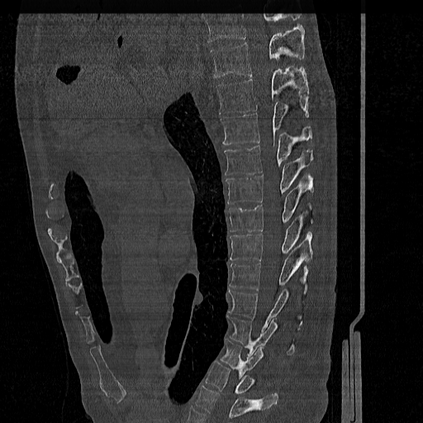

CT reconstruction provides radiologists with images for diagnosis and treatment, yet current deep learning methods are typically limited to specific anatomies and datasets, hindering generalization ability to unseen anatomies and lesions. To address this, we introduce the Multi-Organ medical image REconstruction (MORE) dataset, comprising CT scans across 9 diverse anatomies with 15 lesion types. This dataset serves two key purposes: (1) enabling robust training of deep learning models on extensive, heterogeneous data, and (2) facilitating rigorous evaluation of model generalization for CT reconstruction. We further establish a strong baseline solution that outperforms prior approaches under these challenging conditions. Our results demonstrate that: (1) a comprehensive dataset helps improve the generalization capability of models, and (2) optimization-based methods offer enhanced robustness for unseen anatomies. The MORE dataset is freely accessible under CC-BY-NC 4.0 at our project page https://more-med.github.io/